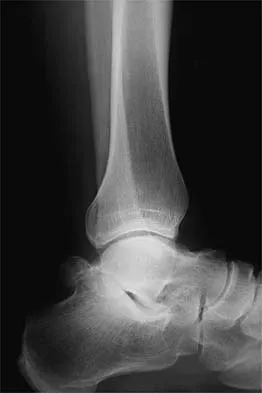

A 26-year-old ballet dancer reports posterolateral ankle pain, especially with maximal plantar flexion. Examination reveals maximal tenderness just posterior to the lateral malleolus, and symptoms are heightened with forced passive plantar flexion. Radiographs are shown in Figures 42a and 42b. What is the most likely cause of the patient's symptoms?

Explanation